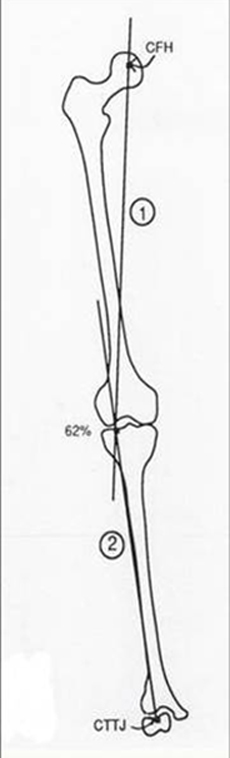

Accurato studio radiografico pre-operatorio per valutare l'entita' ed i gradi della correzione

Nei casi in cui vi sia una severa degenerazione della cartilagine di una sola zona del ginocchio (in genere quella interna) e vi sia associata anche una deformazione in varismo della gamba, in un paziente piuttosto giovane (in genere sotto i 60 anni), vi e' l'indicazione ad effettuare l'intervento di osteotomia della tibia c.d. di "valgizzazione". Tale intervento ha lo scopo ultimo di spostare il carico sul ginocchio dalla zona malata mediale o interna a quella sana laterale. Si tratta quindi, in definitiva, di un intervento "biomeccanico" ovvero un intervento che pur non utilizzando protesi artificiali o altri sistemi di rivestimento biologici, riesce comunque ad apportare un significativo miglioramento sia sul dolore sia sulla funzionalita' del ginocchio.